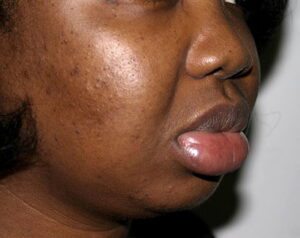

Angioedema is the swelling of deep dermis, subcutaneous or submucosal tissue due to vascular leakage.1 It was first described in 1586.2 Other terms, such as giant urticaria,3 Quincke edema,4 and angioneurotic edema,5 have also been used in the past to describe this condition. Clinically, angioedema is usually nonpitting and nonpruritic. The area of involvement is often skin-colored or slightly erythematous. Depending on the area of swelling, pain can be absent or mild, as in most peripheral or facial swelling, or can be very severe, as in gastrointestinal angioedema. Laryngeal swelling is life-threatening. It should be treated as a medical emergency.

Patients usually describe swelling of the face (eg, eyelids, lips), tongue, hands, and feet. It can be acute or chronic, and each episode of angioedema may last a few hours to a few days. A local burning sensation and pain can be observed without pronounced itchiness or local erythema. Abdominal pain can sometimes be the only presenting symptom of angioedema. Throat tightness, voice changes, and trouble breathing may indicate airway involvement.

For skin involvement, examination can easily identify areas of swelling with or without erythematous skin, often with ill-defined margins. Some cases of angioedema occur in patients with urticaria.

Uvula or tongue swelling can be visualized directly (see image below). However, a laryngoscopy is needed to assess laryngeal or vocal cord involvement.